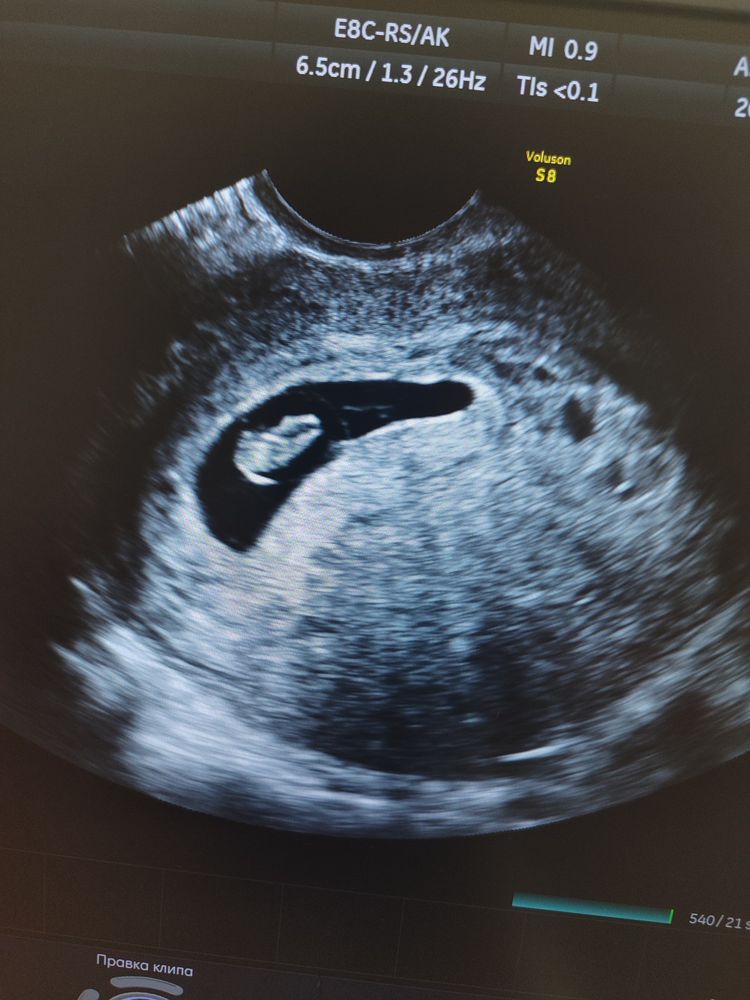

Результаты УЗИ9 дней назад была на УЗИ, было круглое плодное яйцо. Сегодня пошла вытянутое, сказали гипертонус. Сказали нормально так как матка кзади и она выпремляется. Но меня не беспокоят никакие боли, живот мягкий, ничего не мажет. Сб 162 уд/мин. В прошлую беременность неудачную у меня при гипертонусе были дикие боли и каменный живот. Насколько это страшно, не задавит ли он эмбрион? В понедельник иду в свою жк

У меня тоже похожее по форме было ПЯ, тоже ставили тонус, никаких ощущений у меня не было. Врач УЗИ говорила, что матка имеет право сокращаться, в том числе даже на введение вагинального датчика. Сейчас все хорошо, пассажирка пинается в животе.